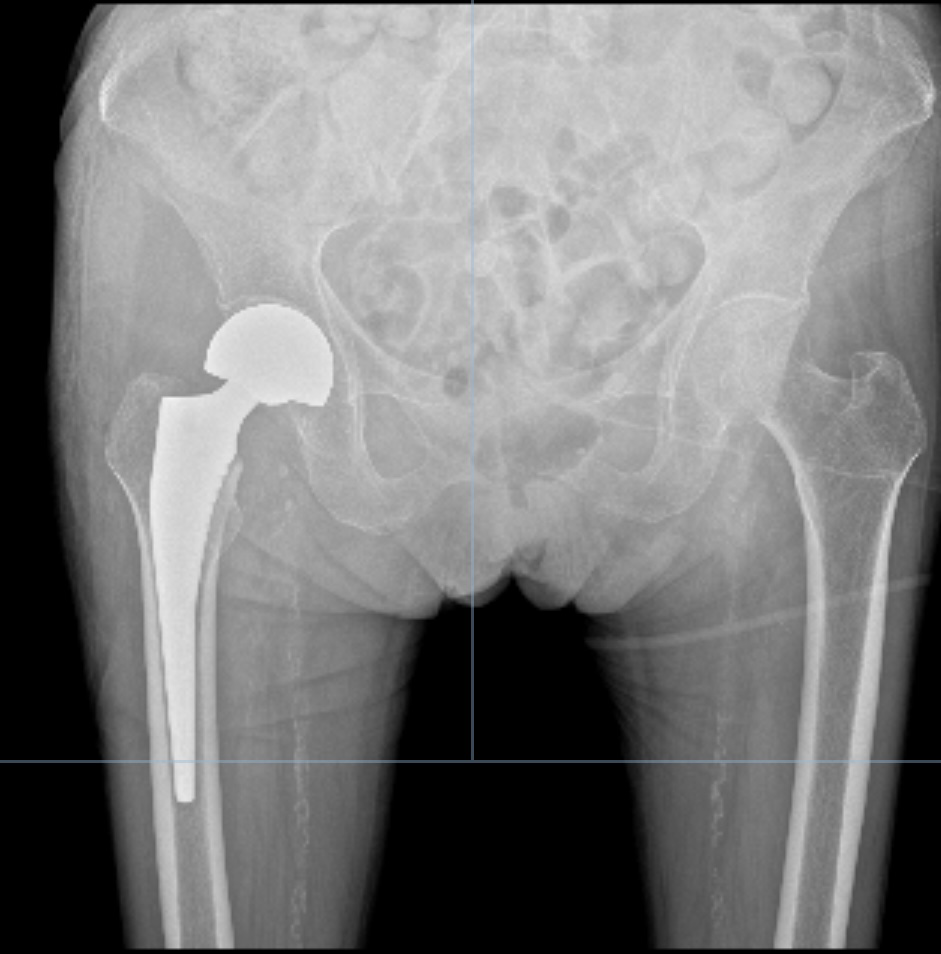

患者为98岁女性,因“右侧股骨颈骨折”入院。此类骨折对老年人健康威胁大,若采取保守治疗需长期卧床,可能引发坠积性肺炎、深静脉血栓、压疮等并发症。因此,尽早手术、恢复行走能力,对改善患者预后具有重要意义。

经过充分准备,李政团队为患者施行“右侧人工股骨头置换术”。手术采用微创方式,力求减少创伤、缩短时间。术中麻醉平稳,出血量少,患者生命体征保持稳定。手术历时约一小时完成。